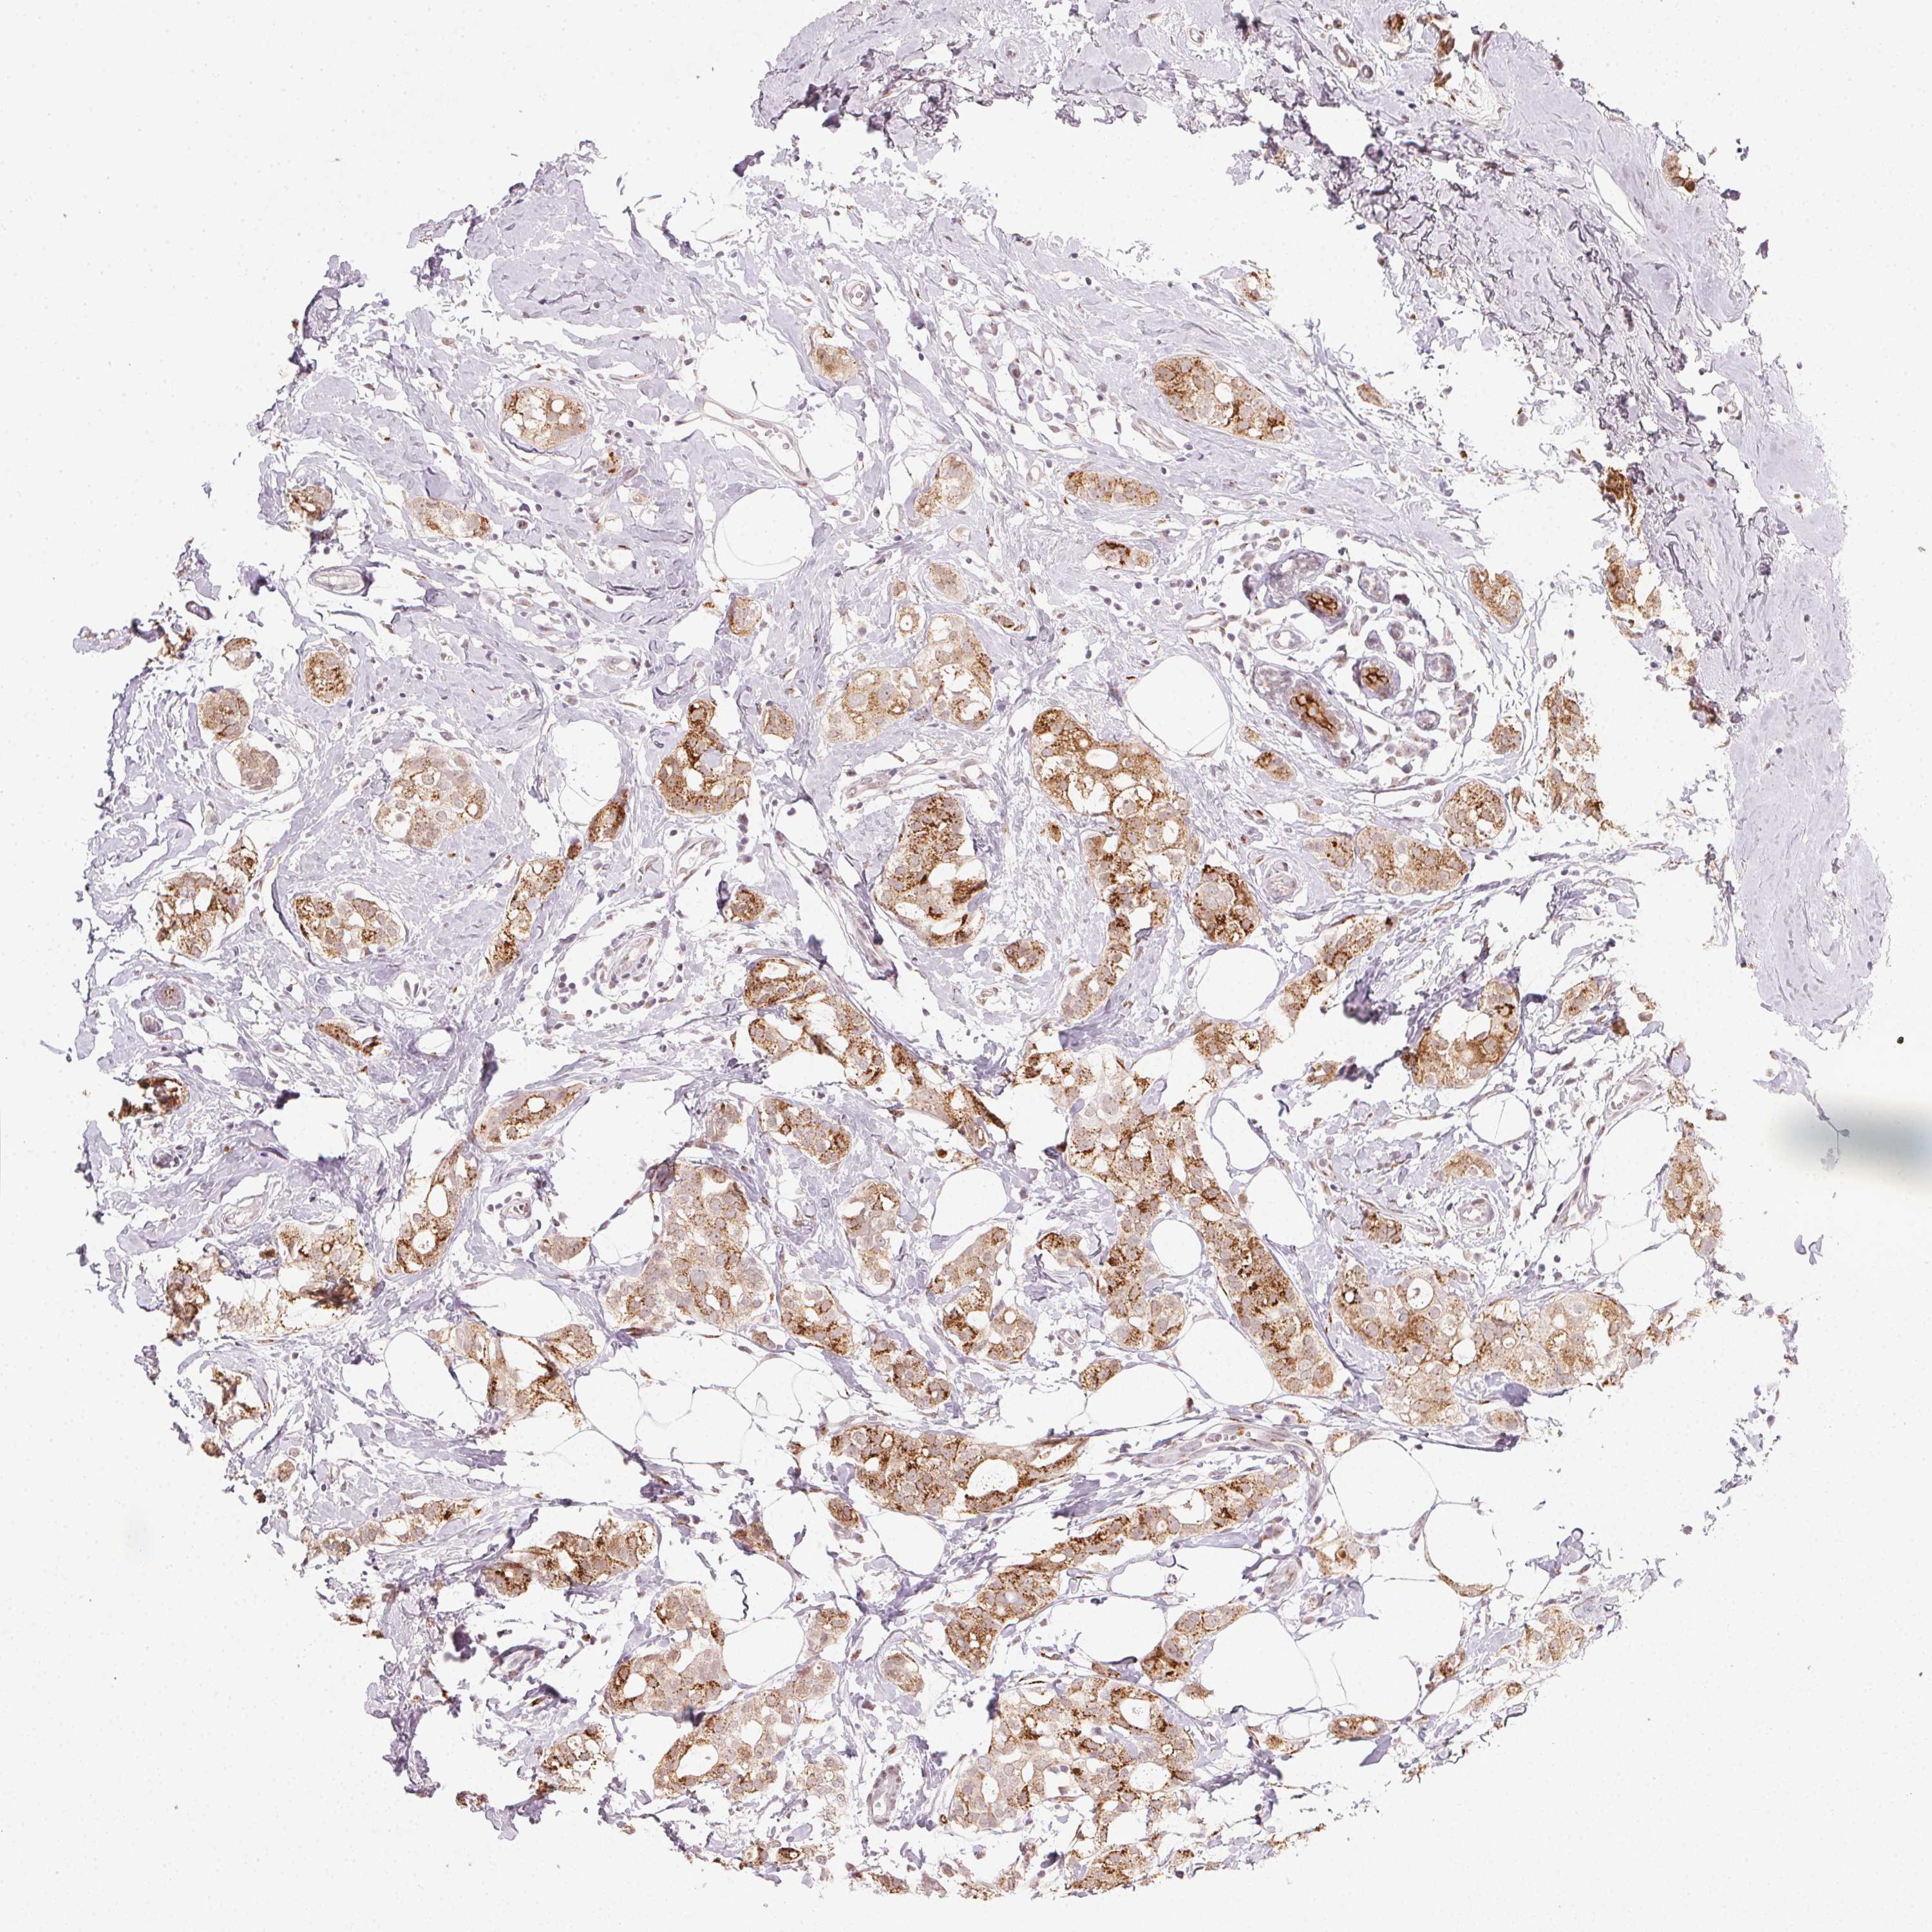

CANCER BREAST CANCER Show tissue menu

BRCA TCGA BRCA VALIDATION PROTEIN EXPRESSION

Breast cancer

Human cancer